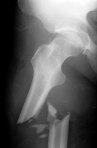

Osteoporosis is when bones are less dense and therefore, are more likely to break, or fracture. White people are at higher risk of osteoporosis than other ethnic groups, but it occurs in all groups. Almost half of all postmenopausal women and 1 out of every 5 men older than 65 years will have osteoporosis-related fracture. Fractures can lead to pain, surgery, loss of independence/mobility, and death.

To prevent osteoporosis take adequate calcium (500 mg 3x/day) and vitamin D (1000 IU a day), exercise, and avoiding tobacco and alcohol. Drugs can prevent osteoporosis, but they are not recommended for general prevention because of their side effects and expense. Instead, the U.S. Preventive Services Task Force (USPSTF) recommends screening for osteoporosis and prescribing drugs only to people who have documented thin bones. Screening involves measuring bone density using dual-energy x-ray absorptiometry (DEXA).

For women OLDER than 65 years the USPSTF recommends osteoporosis screening. (Medicare will currently pay for a DEXA every 2 years). Approximately 9 out of every 100 white women who are 65 years of age with no risk factors for osteoporosis will have an osteoporotic fracture within 10 years.